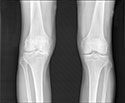

Tested in mice, the probe detected the activity leading to cartilage loss in joints. As the osteoarthritis progressed, the probes’ brightness levels increased.